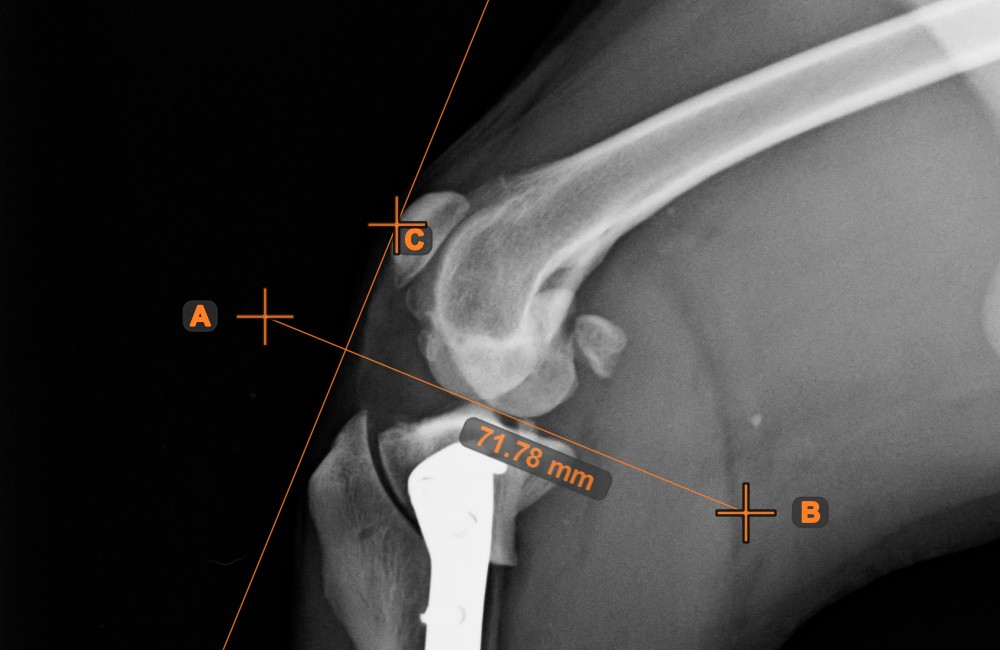

Parallel Line¶

Select the tool from the left toolbar and assign it to one of the available mouse buttons.

Select the base line for the new parallel line from the existing lines on the scene.

Mark the point on the scene where the parallel line will be drawn through.

Modifying the orientation of the base line automatically changes the orientation of the parallel line. Move the parallel line by selecting and moving the point which the line was drawn through.

Distance of Line and Point¶

Measure the distance between a line and a specific point on the scene using the Distance of Line and Point tool.

Select the tool from the left toolbar and assign it to one of the available mouse buttons. Start the measurement by selecting an already existing line from the scene. To complete the measurement, place the desired point on the scene or choose from an already exisiting point. The distance between the line and the point will be automatically calculated.

Modify the measurement by moving any of the points using the Select/Move Item tool.